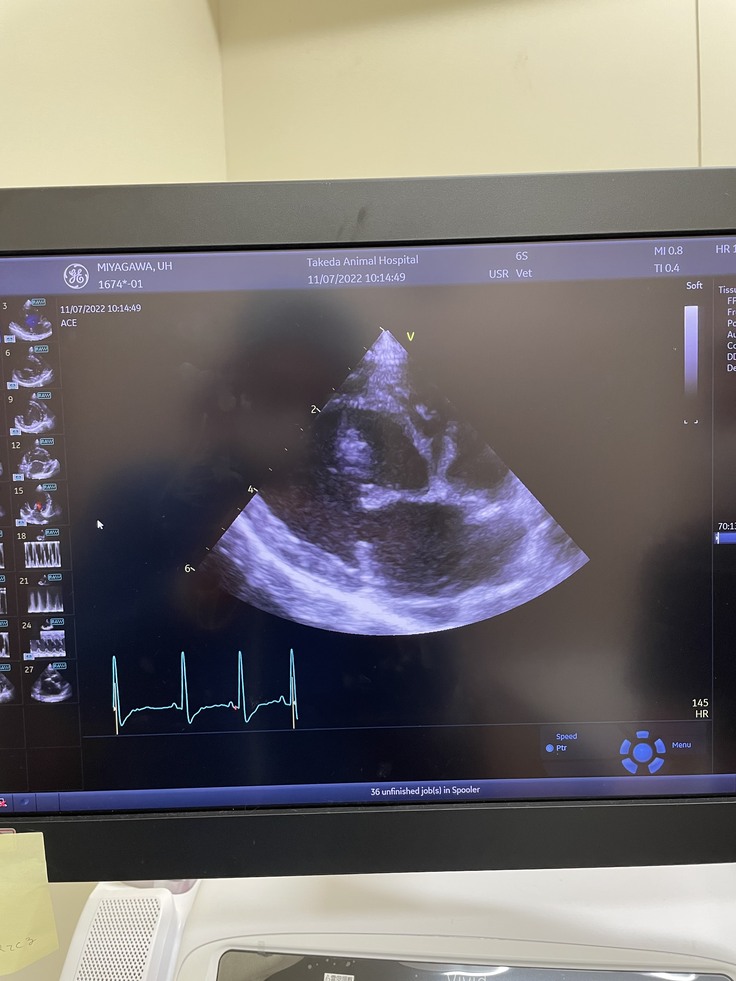

左が健康な心臓です。右が現在のうーちゃんの心臓の状態です。色のついている部分が血液の逆流が見られる箇所になります。僧帽弁閉鎖不全症と診断されてわずか一年ほどで目に見えてわかる程症状が進行していますと主治医の先生から説明がありました。